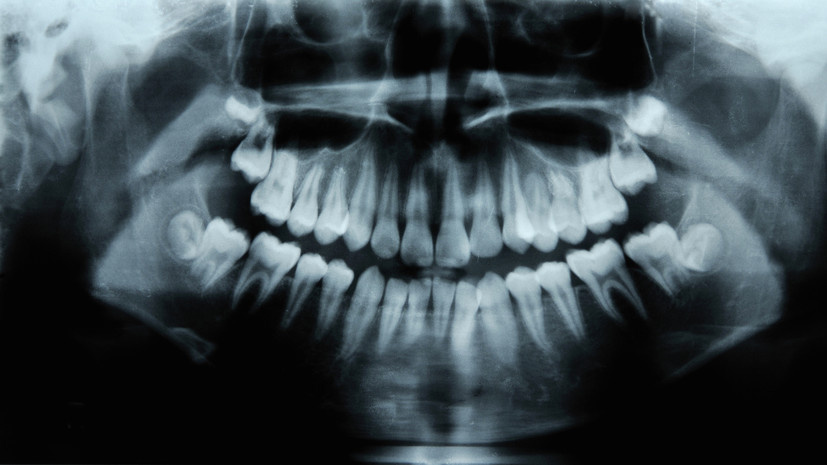

Стоматолог-терапевт, стоматолог-пародонтолог «СМ-Стоматология» Ирина Серёгина рассказала, что отказ от лечения зубов может привести к проблемам с сердцем. В беседе с РИАМО эксперт отметила, что чаще всего запущенный кариес захватывает внутренний слой зуба (дентин) и приближается к пульпе — нервно-сосудистому пучку внутри зуба. По словам специалиста, далее инфекция может распространиться на корень зуба и костную ткань вокруг неё. После чего инфекция из полости рта может попасть с током крови и вызвать инфекционный эндокардит — воспаление клапанов сердца, добавила врач. Ранее хирург, имплантолог, пародонтолог и ортопед Арам Давидян рассказал о влиянии употребления сладостей на развитие кариеса.